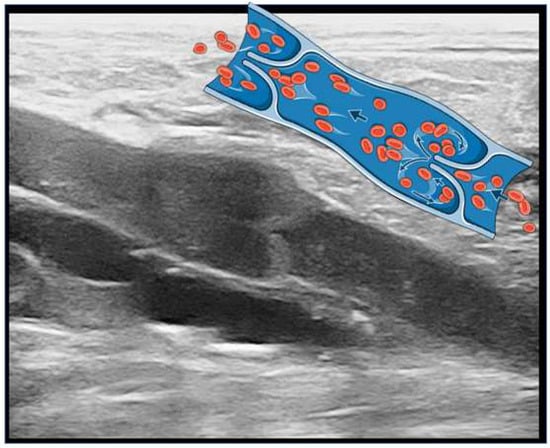

1.4. How Is It Possible to Diagnose CVD?